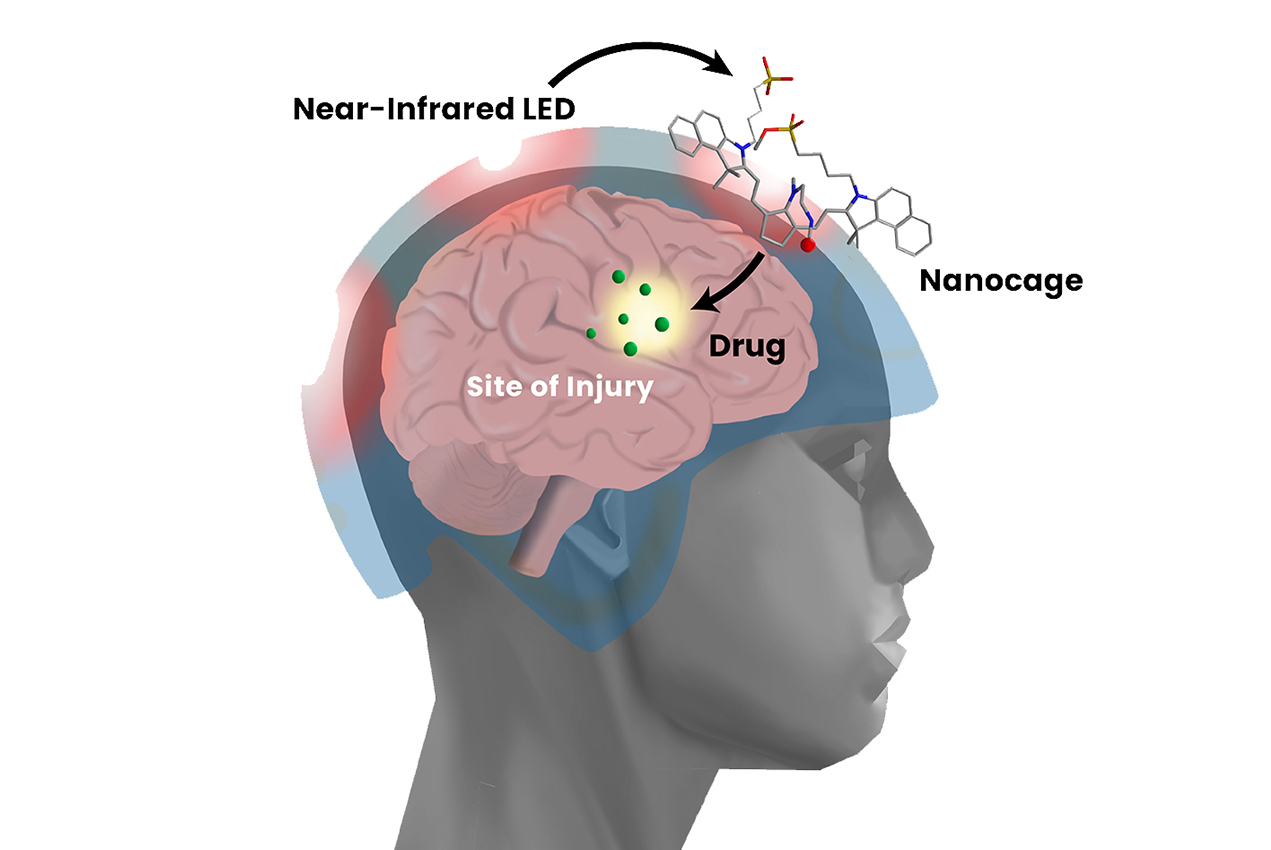

Ferroptosis, tms, neuromodulation, blood brain barriers,. Dha can also reduce endoplasmic reticulum (er) stress and prevent abnormal protein accumulation in the tbi model. After treating the most acute brain injury stages, doctors may recommend treatments such as:

Neurosurgeons can't alter the primary injury suffered by the brain or spinal cord, but they can prevent secondary damage from occurring. The damage can be focal (confined to one area of the brain) or diffuse (happens in more. For severe tbis, treatment may include medication, surgery, and rehabilitation.

Treatment treatment is based on the severity of the injury. The need for imaging is based on a physical examination by a doctor and a person's symptoms. While there is no standard treatment for reversing brain damage, there are a few different therapies that have demonstrated efficacy in a handful of patients.